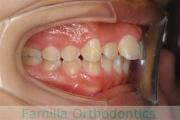

No.19V-044

- 主な症状:

- 上顎前突

- 年齢:

- 13歳

- 性別:

- 女性

- 抜歯部位

- 上:

- 44

- 下:

- 8558

- 主な使用装置:

- FEA

- 治療にかかった費用:

- 85万円

出っ歯を治したいということで小学生の時に来院されました。中学生になるまで経過観察をして、診断、上下左右から小臼歯を抜歯してマルチブラケット法にて治療を行いました。2年強、30回程度の通院が必要でした。

口元の突出感も大きく改善しています。

- ≫治療前

- ≫治療後

上下とも前歯の叢生(でこぼこ、凹凸、ガタガタ)がありましたので、保定をしっかりやらないと後戻りのリスクが出てきます。